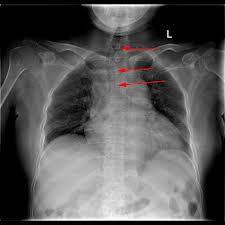

當一側胸腔積液、積氣或有占位性新生物時,由於患側胸內壓力增高而將氣管推向健側;當一側肺不張、胸膜增厚及粘連時,氣管被牽拉向患側